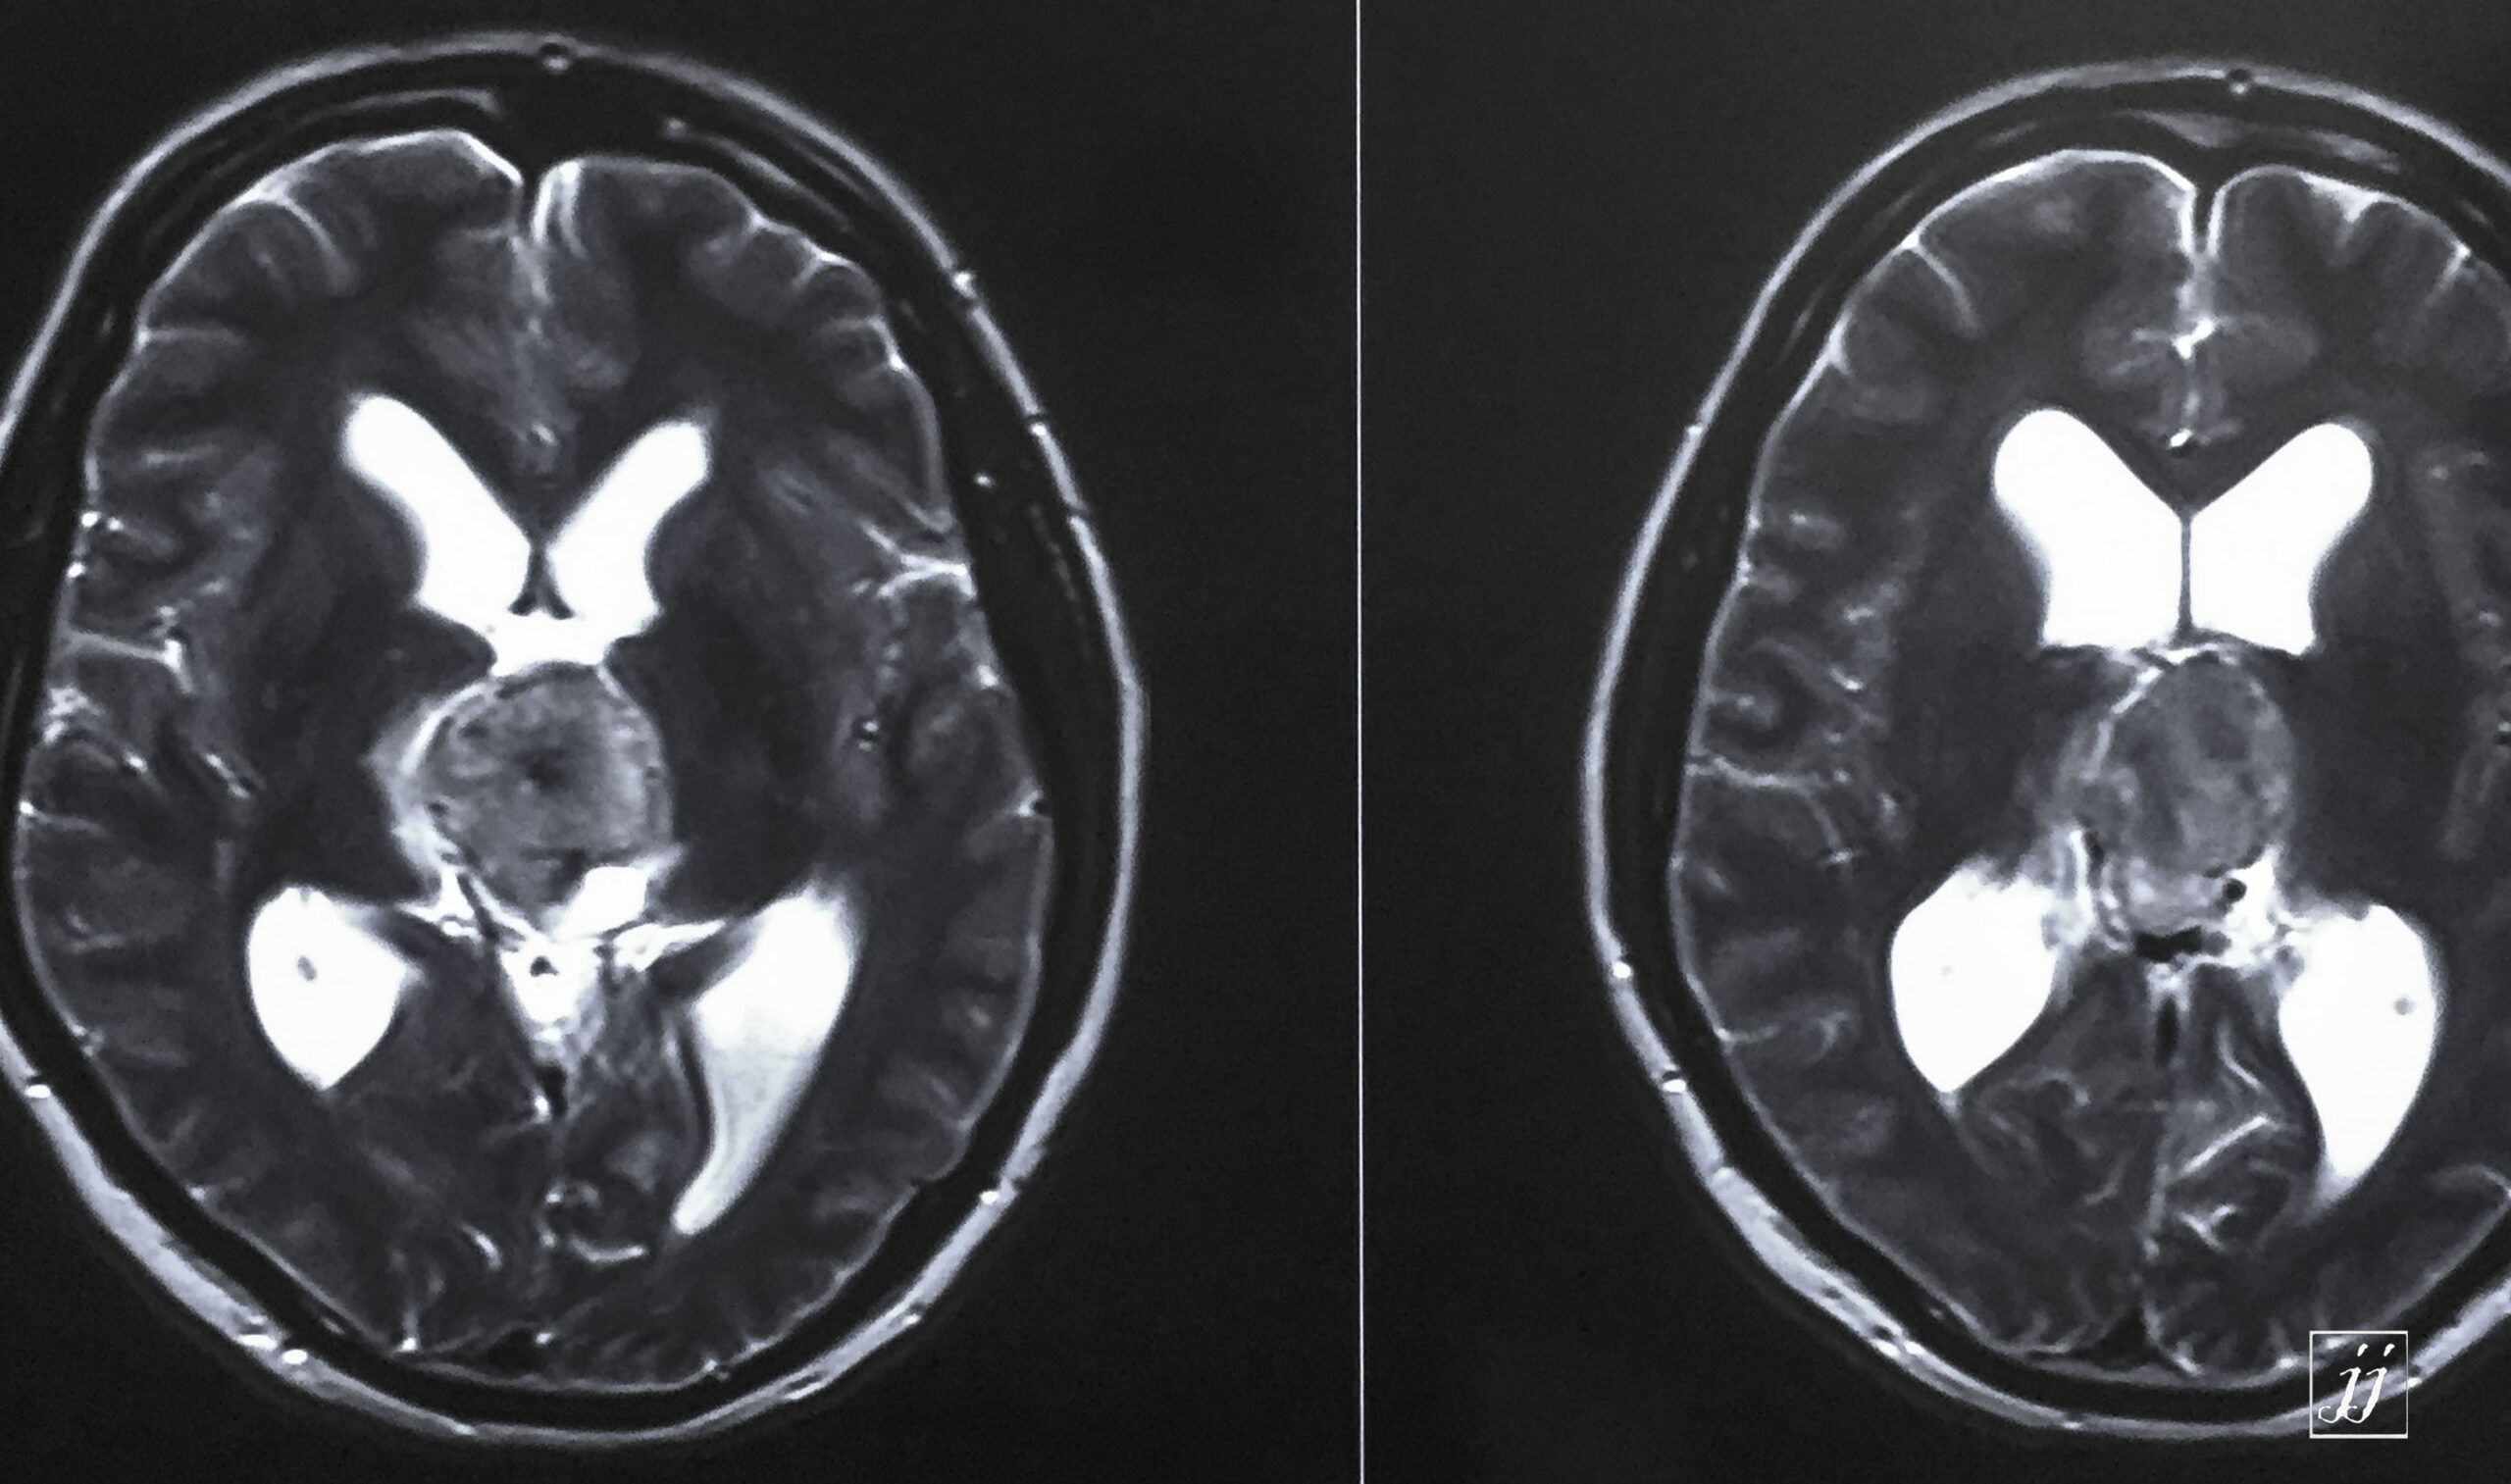

Brain- hugged size tectal and quadrigeminal meningioma (11)